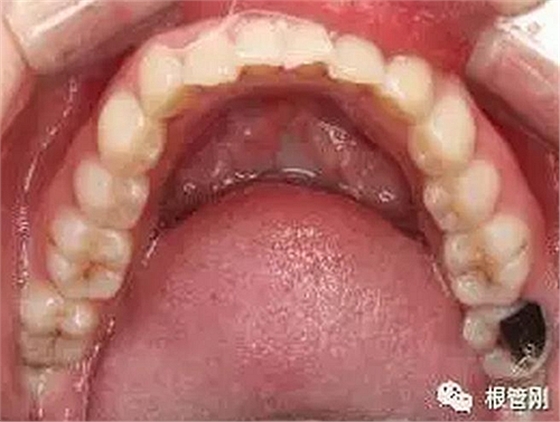

這是一顆嚴(yán)重的蛀牙,顏色發(fā)黑,牙齒的一半已經(jīng)崩解,看到此情此景,也許很多人會想它的神經(jīng)肯定死掉了吧?它還有救嗎?應(yīng)該會做根管治療+牙冠修復(fù)吧?

經(jīng)細(xì)致的詢問病史(有沒有自發(fā)痛,冷熱刺激敏感等)、仔細(xì)的檢查(包括探診,冷診,熱診,叩診以及牙片的檢查不可缺少),綜合各種信息判斷,得出準(zhǔn)確的診斷為深齲,在與患者溝通,患者同意直接樹脂修復(fù)!